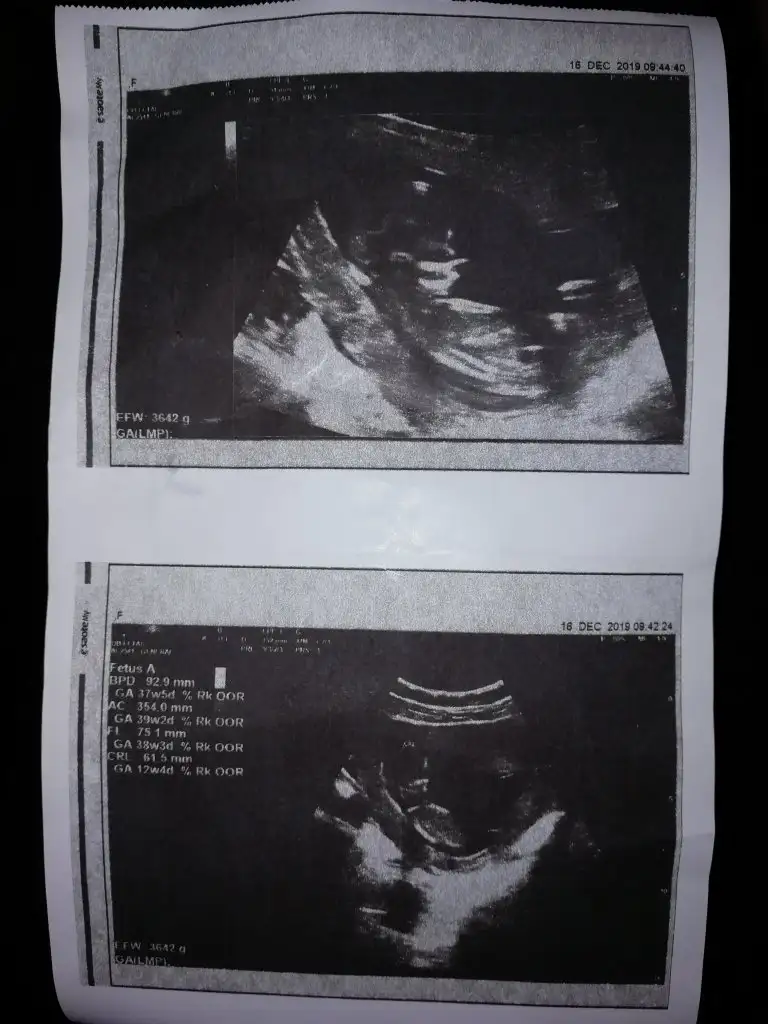

Ikılı test ıcın kan verdık 15gun sonra ogrenıcem sonucu. Dr amca ense kalınlığı 1.5 dedi gayet ıyı dedı boyunuda dedı burun kemiğide guzel dedı hatta 1kılo almış neredeyse dedı folık asıtı bırakabilirsin dedı vitamin yazdı devıt 3 verdıgıni soyledım saglik ocagının tmm kullan dedı ay o kadar cok sey sordum soyledıki şükür hersey yolunda dedı ve benım kuzucum kıpır kıpırdı yuzunu bı bize döndu elleri ayakları cama yapışır gb bıde yan dondu nasıl buyumuş ben şok oldum.

MaşAllah canım gözün aydın güzel haberler almışsın ❤Arkadaslar buda 13 +2 haftalık ultrasonumuz tabı bıraz karanlık cıkıyor hep oysa gorunce yakından ne kadar netti.bu devletin malzemeleride sıkıntılı Allahtan Dr um kafa dengısızcede erkek mi ☺Eki Görüntüle 2565666

Masaalh ya haftaya pazartesi bende 13 hafta 3 günlük olucam umarım bana da cinsiyet söyler drmArkadaslar buda 13 +2 haftalık ultrasonumuz tabı bıraz karanlık cıkıyor hep oysa gorunce yakından ne kadar netti.bu devletin malzemeleride sıkıntılı Allahtan Dr um kafa dengısızcede erkek mi ☺Eki Görüntüle 2565666